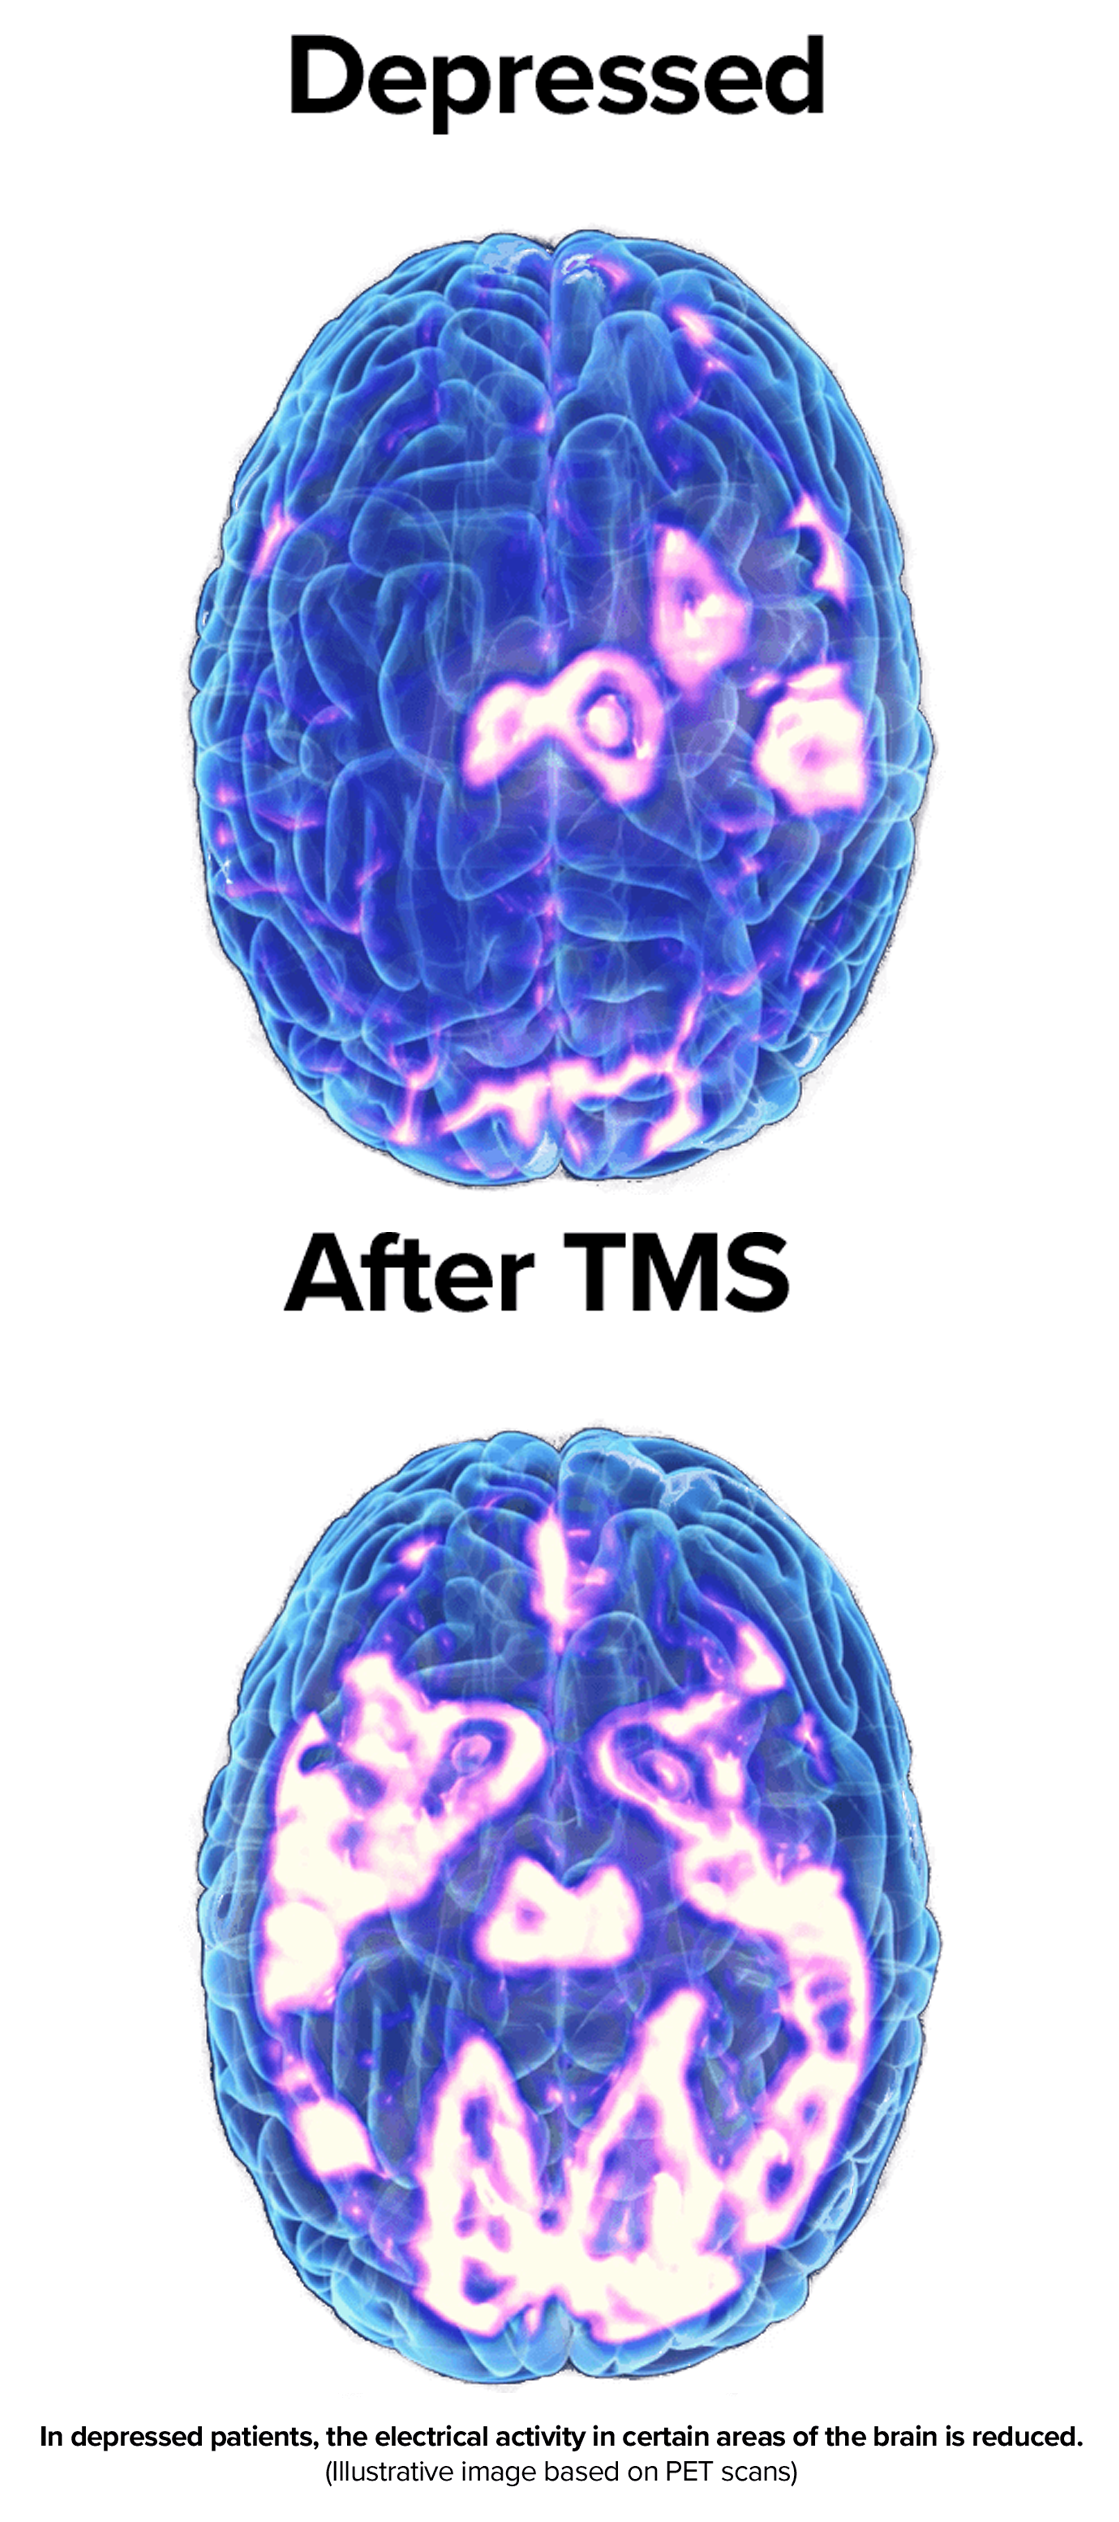

Approximately 58% of patients with treatment-resistant MDD respond positively to TMS therapy! TMS therapy involves the use of short pulses of magnetic energy to stimulate nerve cells in the brain. These pulses are delivered to the area in the brain that researchers believe are responsible for emotional judgment and mood regulation. All of our TMS Therapy is performed with a Dr. in the office to ensure a safe treatment environment.

While there are several theories about what causes depression, the condition most likely results from a complex interplay of individual factors, one of the most widely accepted explanations cites abnormal brain chemistry.

Researchers have suggested that for some people, having too little of certain substances in the brain (called neurotransmitters) could contribute to depression. Restoring the balance of brain chemicals could help alleviate symptoms, Transcranial Magnetic Stimulation (TMS) is non-invasive and nonsystemic (non-drug) method to help restore this balance.